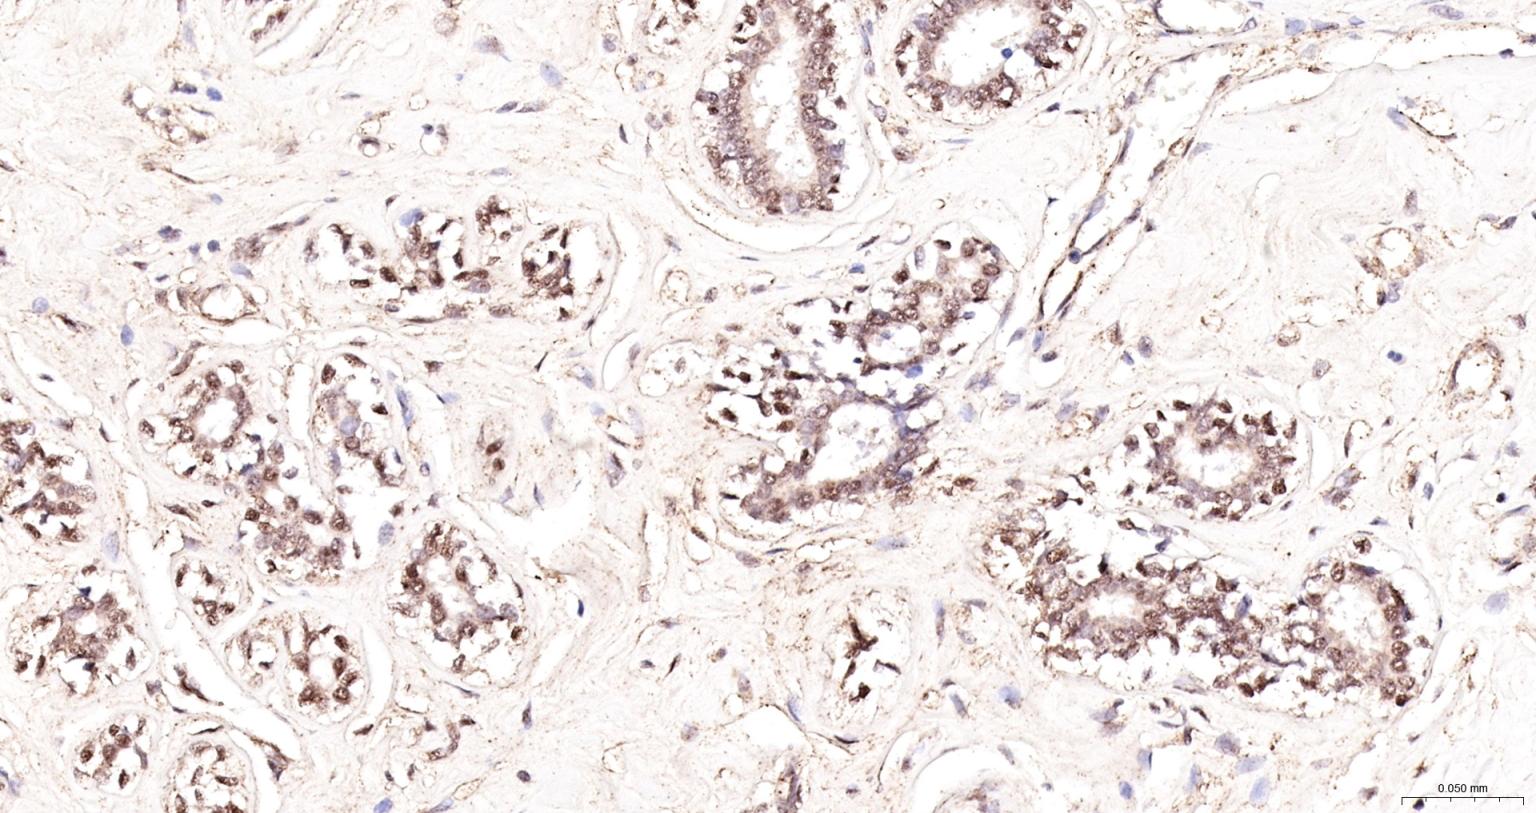

Paraformaldehyde-fixed, paraffin embedded Mouse Testicles; Antigen retrieval by boiling in sodium citrate buffer (pH6.0) for 15 min; The section was incubated with UBN1 Polyclonal Antibody, Unconjugated (bs-34193R) at 1:200 overnight at 4°C, followed by conjugation to the bs-0295G-HRP and DAB (C-0010) staining.